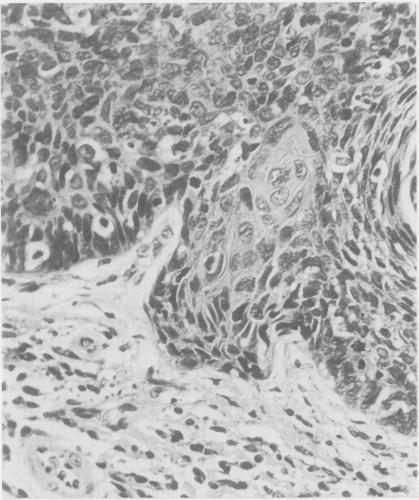

The pathological, cytological, and clinical features of vulvar intraepithelial neoplasia (VIN) are described. The rate of progression of VIN III to an invasive carcinoma is very low and spontaneous regression can occur. These features prevent the drawing of a direct analogy between vulvar and cervical intraepithelial neoplasia. The concept of microinvasive carcinoma of the vulva is discussed, and it is concluded that no satisfactory definition of this entity has been achieved.

本文描述了外阴上皮内瘤变(VIN)的病理、细胞学及临床特征。VIN III进展为浸润性癌的发生率很低,且可发生自发消退。这些特征使得外阴上皮内瘤变与宫颈上皮内瘤变无法直接进行类比。文中对外阴微浸润癌的概念进行了讨论,得出的结论是尚未对该实体达成令人满意的定义。